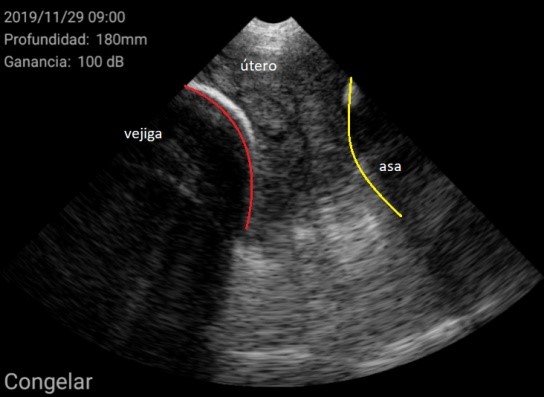

Por otra parte, la figura 3, muestra a una cerda nulípara púber, con un aparato reproductor desarrollado y apta para ser cubierta.

Figura 3. Cerda púber

Figura 4. Nulípara en proestro, ovario con folículos.